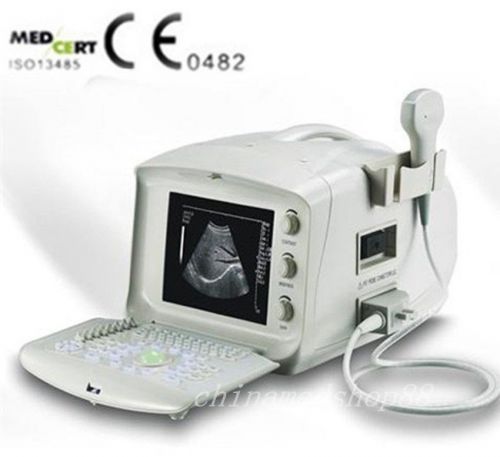

2015 New Digital Portable Ultrasound Scanner +Convex Probe +3D work Station

2015 new Digital Portable Ultrasound Scanner machine with Convex Probe +3D